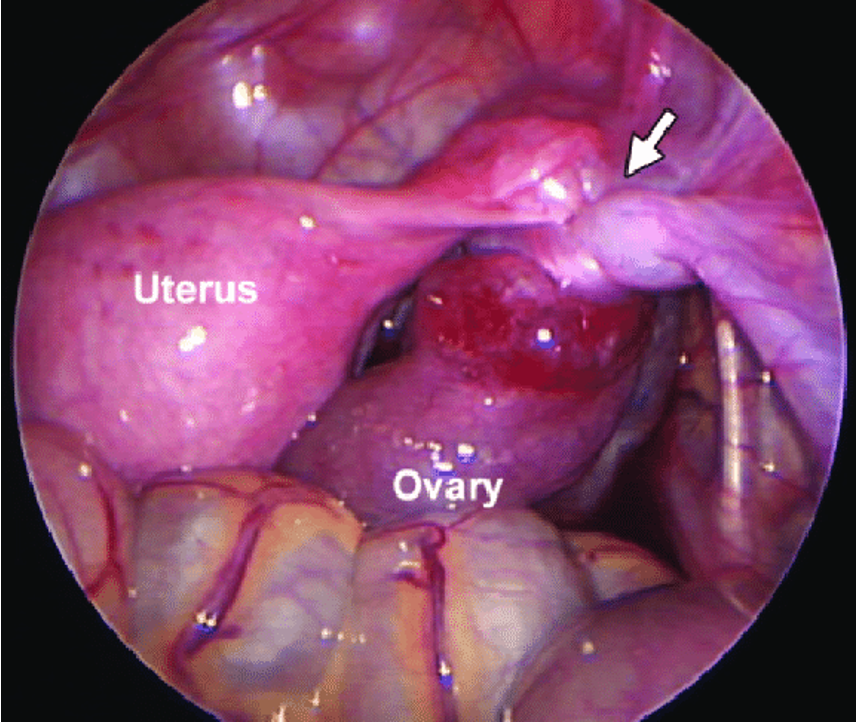

Ruptured Ectopic Pregnancy

Laproscope

Twiset ovary torsion